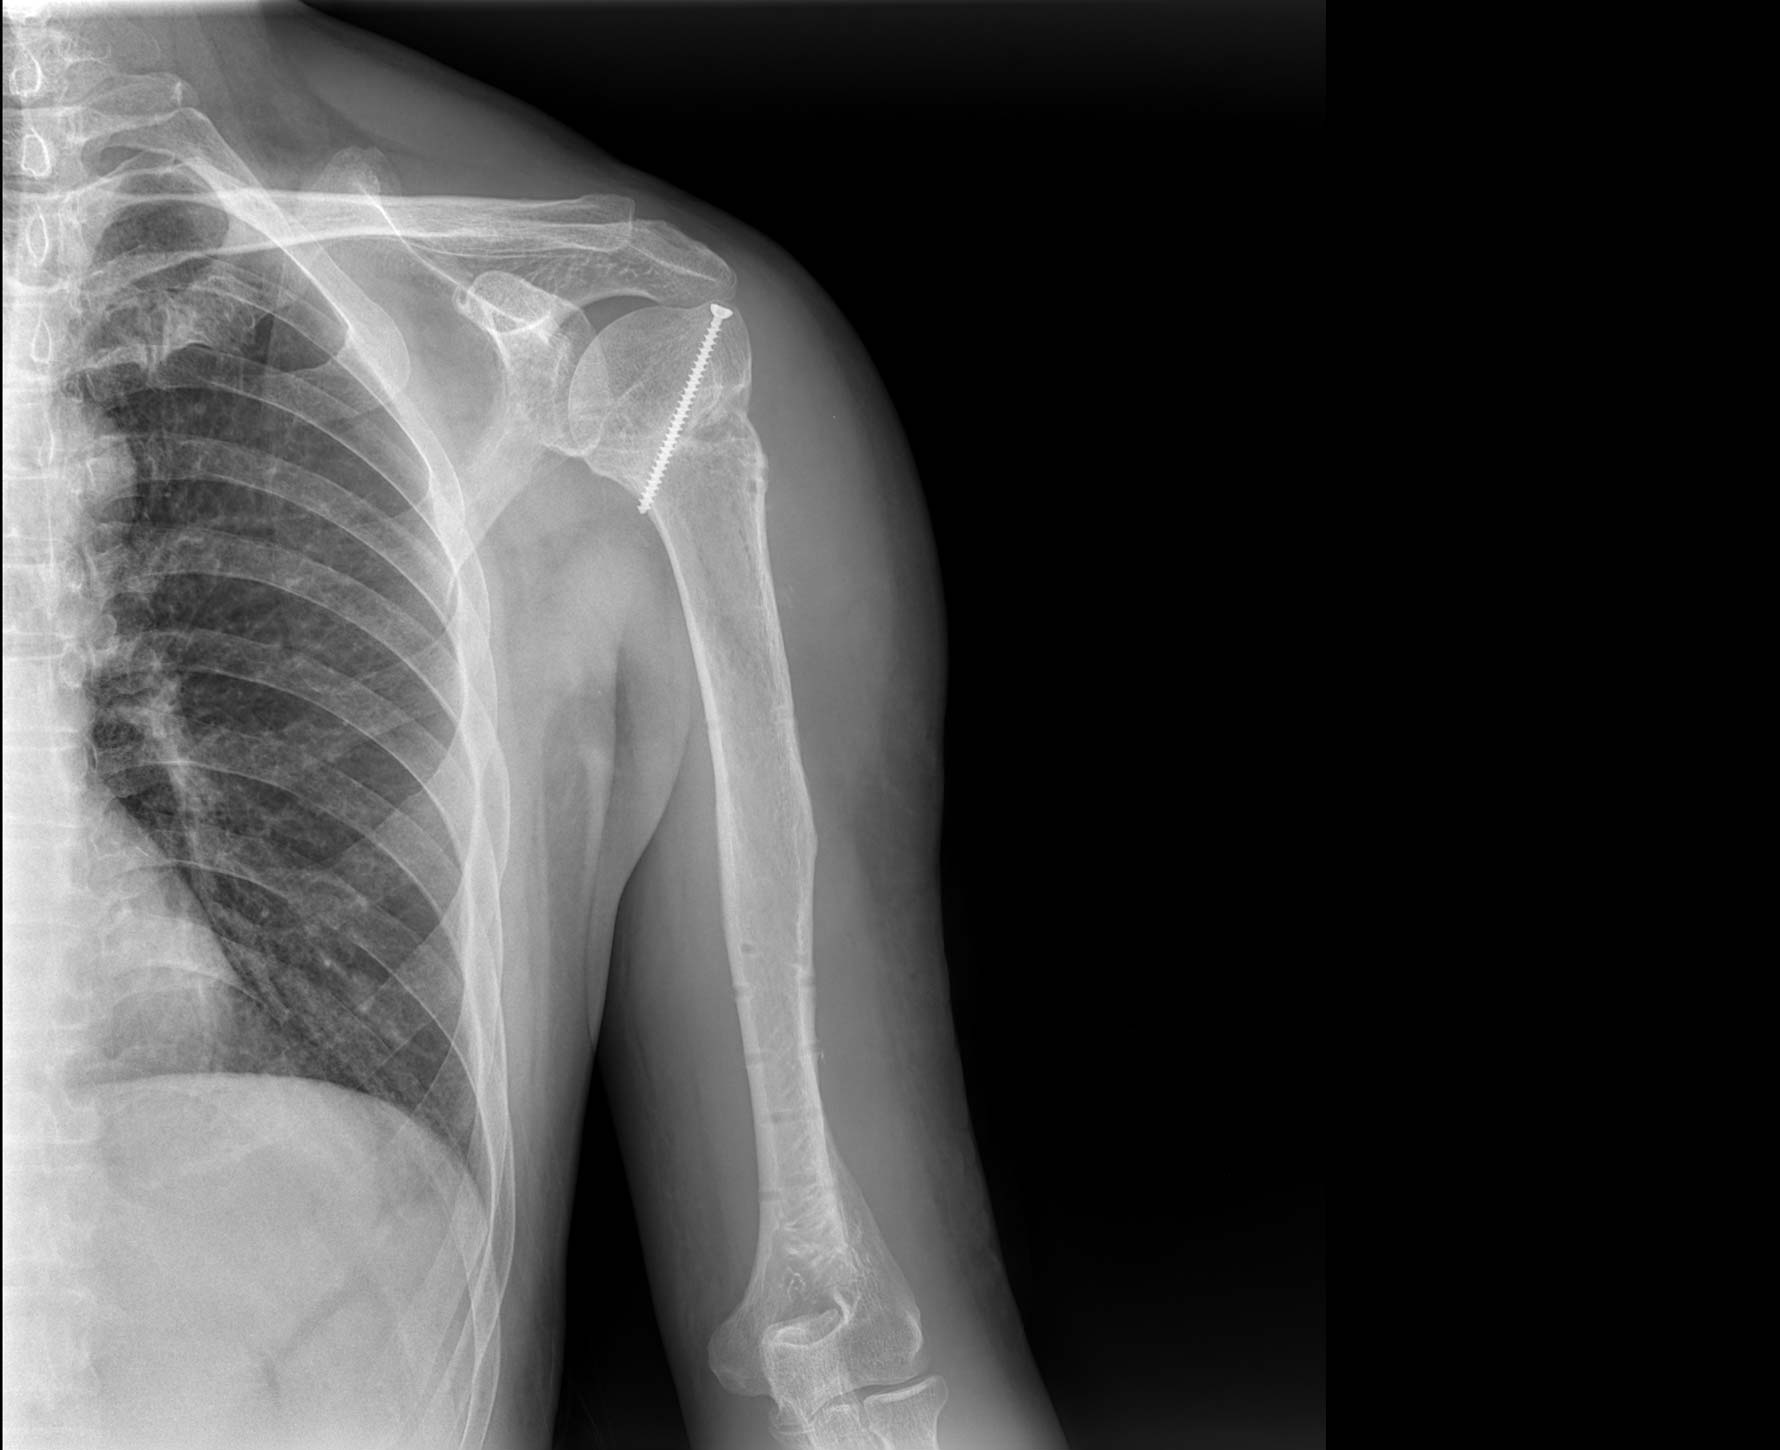

• 拍片

适用于全身各部位摄影

(常规摄影和特殊摄影)

临床图像